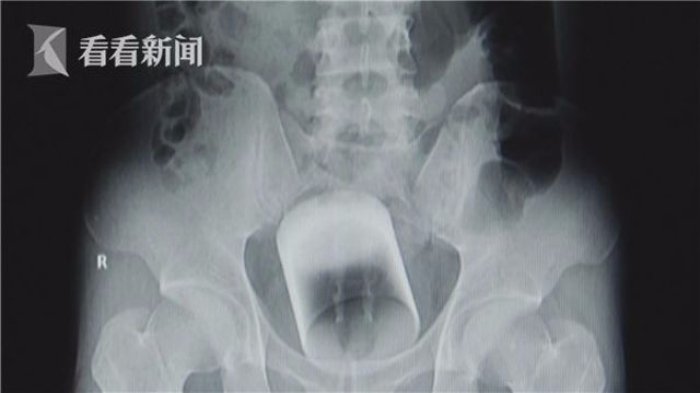

Tim dokter bedah di Guangzhou, China berhasil mengeluarkan gelas kaca dari anus seorang pria.

TRIBUNWOW.COM - Tim dokter bedah di Guangzhou, Cina berhasil mengeluarkan gelas kaca dari anus seorang pria.

Dengan segera dokter merontgen untuk mengetahui penyebab sakitnya pria itu.

Dokter pun terkejut menemukan sebuah gelas tersangkut di bokongnya.

Yang lebih mengherankan, gelas itu terbuat dari kaca dengan tinggi 8 cm dan berdiameter 7 sentimeter.

Posisi gelas itu berada pada bagian atas anusnya dan bisa menyebabkan kematian jika tidak segera diambil.